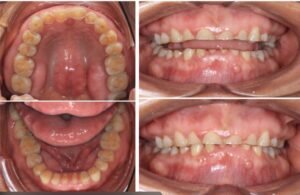

Si el bruxismo se mantiene en el tiempo puede generar sobrecarga de la ATM, inflamación muscular crónica, desgaste dental progresivo, fracturas dentarias, alteraciones posturales y dolor

orofacial persistente. Por eso el diagnóstico temprano es fundamental.